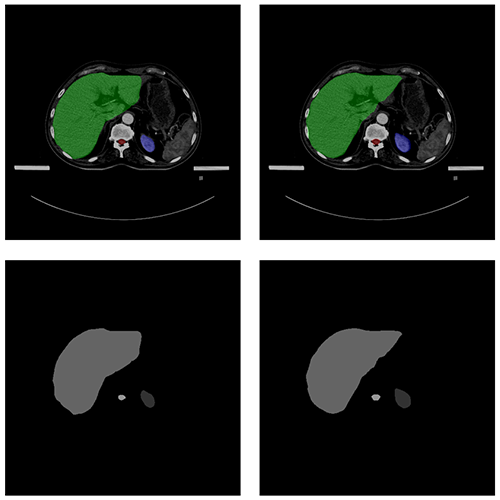

自動(dòng)勾畫效果

AUTOMATIC CONTOURING

原圖

預(yù)測圖